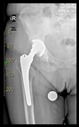

The guiding wire was inserted and controlled with fluoroscopy flashes (Figure 4). The drilling and reaming were carried out in accordance with the recommendations:

Figure 4.

The biocompatible aiming device after insertion of the guiding wire.

The direction of the cup stem was determined by the guide wire. The aiming device was needed to introduce this wire. After removing the aiming device, the next step was the drilling. Since a cannulated drill bit was used, the previously installed wire could guide the process. A self-positioning reaming tool was then used in the drilled channel. In the prepared cavity, the cup was fitted perfectly. Of the two stemmed cups available to us, the McMinn cup (Waldemar Link, Hamburg, Germany) had the simpler geometry and was therefore chosen. The stemmed cup was inserted according to the manufacturer’s recommendation. In the presence of a significant bone defect, a synthetic bone graft may be impacted for substitution.

The radiological examination allowed us to verify the close bone-to-implant contact and the unchanged position of the implant during follow-up.

In all the cases operated with the above-described targeting procedure, the stems of the cups remained between the cortical bone surfaces without perforation of the linea terminalis, as shown by postoperative radiographs. There were no complicated surgical situations. In 16 cases, the wound healings were uneventful, and the hips were able to bear weight again after postoperative rehabilitation.